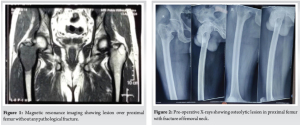

A 43-year-old male presented with the chief complaints of pain and inability to bear weight over his right lower limb. He had a history of falling from stairs 3 months ago, after which he developed pain in his right hip but was still able to perform all activities. A magnetic resonance imaging (MRI) done outside at the time of injury suggested the presence of an expansile lytic lesion measuring approximately 5.6 × 4.1 cm in the meta-diaphyseal region of the proximal femur, primarily involving the greater trochanter, with no evidence of a pathological fracture (Fig. 1).

One day prior to the presentation, the patient experienced sudden pain in his right hip while performing hip movements. Upon evaluation, the patient’s right lower limb was found to be in extension, abduction, and external rotation. Radiological examination revealed a fracture of the femoral neck along with a lytic lesion in the proximal femur (Greater trochanter region) on the right side (Fig. 2). An MRI of the pelvis with both hip joints was performed to assess the extent of the lesion. The results indicated an expansile, lobulated soft tissue mass involving the greater trochanter of the right femur, extending into the femoral neck. This was associated with cortical thinning and a pathological fracture of the femoral neck, suggesting a possible GCT (Fig. 3).